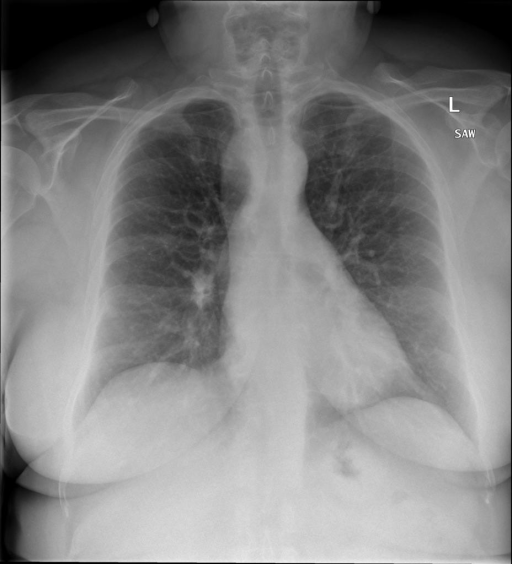

## 本文贡献  - 借助ChatGPT以及公开的数据集,我们构造了一个`X光影像-诊断报告`对的医学多模态数据集; - 我们将构建的中文胸部X光片诊断数据集在[VisualGLM-6B](https://github.com/THUDM/VisualGLM-6B)进行微调训练,并开放了部分训练权重用于学术研究; ## 数据集 - [MIMIC-CXR](https://physionet.org/content/mimic-cxr-jpg/2.0.0/)是一个公开可用的胸部X光片数据集,包括377,110张图像和227,827个相关报告。 - [OpenI](https://openi.nlm.nih.gov/faq#collection)是一个来自印第安纳大学医院的胸部X光片数据集,包括6,459张图像和3,955个报告。 在上述工作中,报告信息都为非结构化的,不利于科学研究。为了生成合理的医学报告,我们对两个数据集进行了预处理,并最终得到了可以用于训练的**英文报告**。除此之外,为了更好的支持中文社区发展,借助ChatGPT的能力,我们将英文报告进行了中文翻译,并最终形成了可用于训练的数据集。 |数据集|数量|下载链接| |:-|:-|:-| |MIMIC-CXR-zh|-|-| |OpenI-zh|6,423|[诊疗报告](./data/Xray/openi-zh.json) 、[X光影像](https://pan.baidu.com/s/13GBsDMKf6xBZBSHpoWH_EA?pwd=k9sh)| ## 快速上手 1. 安装环境 ```bash # 安装依赖 pip install -r requirements.txt # 国内换源安装依赖 pip install -i https://mirrors.aliyun.com/pypi/simple/ -r requirements.txt ``` 此时默认会安装`deepspeed`库(支持`sat`库训练),此库对于模型推理并非必要,同时部分`Windows`环境安装此库时会遇到问题。 如果想绕过`deepspeed`安装,我们可以将命令改为: ```bash # 安装依赖 pip install -i https://mirrors.aliyun.com/pypi/simple/ -r requirements_wo_ds.txt # 安装SwissArmyTransformer pip install -i https://mirrors.aliyun.com/pypi/simple/ --no-deps "SwissArmyTransformer>=0.3.6" ``` 2. 模型推理 CLI推理: ```python python cli_demo.py --from_pretrained checkpoints/finetune-XrayGLM-05-25-01-04 --prompt_zh '详细描述这张胸部X光片的诊断结果' ``` 更多[参数](https://github.com/WangRongsheng/XrayGLM/blob/main/cli_demo.py#L16) ## 效果展示 影像诊断: |X光影像|诊疗报告(医生)|XrayGLM| |:-|:-|:-| ||根据X射线图像,心脏大小正常,肺部看起来很清晰。已经排除了肺炎、积液、水肿、气胸、腺病、结节或肿块的存在。该发现表明一切正常。换句话说,总体印象是胸部正常。|X光片显示,心脏大小正常。肺部没有气胸或胸腔积液的证据。骨骼结构看起来没有任何异常。总的来说,X光片表明没有发现急性心肺疾病的迹象。| ||X光图片显示没有扭曲的区域、可疑的骨质不透明度或胸腺积液。心脏大小轻微增大,但非常稳定。此外,没有气胸的证据,肺野也正常。总体来说,X光片显示没有急性心脏异常,但要注意轻微的心脏扩大。|X光片显示,心脏大小正常。肺部和纵隔轮廓清晰,没有气胸或胸腔积液的证据。骨骼结构完整,没有任何急性异常。| ||心影形态在正常范围内。没有急性骨质异常。有可能出现没有明显的吸水或肺实质状况的线索。没有大面积积液或气胸。有可能怀疑其有误吸或肺实质问题。为了确诊和治疗,可能需要进行适当的影像学随访。|心脏大小正常,肺部和纵隔轮廓清晰。没有急性异常或活动受限的证据。没有任何明显的气胸、胸腔积液或肺不张的迹象。此外,也没有发现任何局灶性骨质异常或其他急性疾病。| 多轮对话: |X光影像|诊疗报告(医生)| |:-|:-| ||右侧主动脉突出观察到。心脏大小正常。胸部未发现明显的肺气肿、胸膜积液或可疑的肺部病变。报告指出已知右侧主动脉情况正常。| ```bash >> X光影像路径:./data/Xray/861_1.png >> 用户:这是一张什么图? >> XrayGLM:这张图片显示的是一张肺部检查的X光片。 >> 用户:请描述这张胸部X光片的诊断结果 >> XrayGLM:心脏大小正常,肺部清晰。没有急性心肺疾病的证据。 >> 用户:是否存在肺气肿? >> XrayGLM:没有肺气肿。心脏大小正常,肺部清晰。没有发现急性心肺疾病的证据。 >> 用户:平时饮食该注意什么? >> XrayGLM:饮食应该健康,均衡。建议增加蛋白质的摄入量,因为蛋白质有助于维持肌肉和骨骼的健康。多食用蔬菜、水果、全谷物以及健康的脂肪来源如橄榄油、鱼类等可以帮助获得足够的维生素和矿物质。此外,避免过度饮酒或吸烟,这些习惯可能会对心脏健康产生负面影响。 ``` ## 项目致谢 1. [VisualGLM-6B](https://github.com/THUDM/VisualGLM-6B)为我们提供了基础的代码参考和实现; 2. [MiniGPT-4](https://github.com/Vision-CAIR/MiniGPT-4)为我们这个项目提供了研发思路; 3. ChatGPT生成了高质量的中文版X光检查报告以支持XrayGLM训练; 4. [gpt_academic](https://github.com/binary-husky/gpt_academic)为文档翻译提供了多线程加速; 5. [MedCLIP](https://github.com/RyanWangZf/MedCLIP) 、[BLIP2](https://huggingface.co/docs/transformers/main/model_doc/blip-2) 、[XrayGPT](https://github.com/mbzuai-oryx/XrayGPT) 等工作也有重大的参考意义;  这项工作由[澳门理工大学应用科学学院](https://www.mpu.edu.mo/esca/zh/index.php)硕士生[王荣胜](https://github.com/WangRongsheng) 、[段耀菲](https://github.com/IsBaSO4) 、[李俊蓉](https://github.com/lijunrong0815)完成,指导老师为檀韬副教授、[彭祥佑](http://www.patrickpang.net/)老师。 *特别鸣谢:[USTC-PhD Yongle Luo](https://github.com/kaixindelele) 提供了有3000美金的OpenAI账号,帮助我们完成大量的X光报告翻译工作 ## 免责声明 本项目相关资源仅供学术研究之用,严禁用于商业用途。使用涉及第三方代码的部分时,请严格遵循相应的开源协议。模型生成的内容受模型计算、随机性和量化精度损失等因素影响,本项目无法对其准确性作出保证。即使本项目模型输出符合医学事实,也不能被用作实际医学诊断的依据。对于模型输出的任何内容,本项目不承担任何法律责任,亦不对因使用相关资源和输出结果而可能产生的任何损失承担责任。 ## 项目引用 如果你使用了本项目的模型,数据或者代码,请声明引用: ```bash @misc{wang2023XrayGLM, title={XrayGLM: The first Chinese Medical Multimodal Model that Chest Radiographs Summarization}, author={Rongsheng Wang, Yaofei Duan, Junrong Li, Patrick Pang and Tao Tan}, year={2023}, publisher = {GitHub}, journal = {GitHub repository}, howpublished = {\url{https://github.com/WangRongsheng/XrayGLM}}, } ``` ## 使用许可 此存储库遵循[CC BY-NC-SA](https://creativecommons.org/licenses/by-nc-sa/4.0/) ,请参阅许可条款。